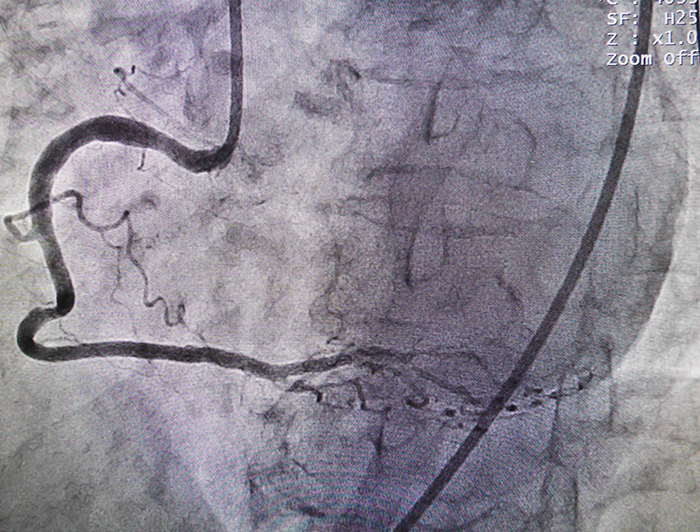

According to the National Institutes of Health, doctors perform PCI to open coronary arteries that are narrowed or blocked by the buildup of atherosclerotic plaque. PCI may be used to relieve symptoms of coronary heart disease or to reduce heart damage during or after a heart attack.

The HeartMate PHP cardiac assist device is placed via catheter to temporarily assist circulation by continuously pumping blood during PCI. Unlike traditional catheter-based support devices, the HeartMate PHP cardiac assist device can generate an average blood flow of four to five liters per minute, which is the normal amount of blood pumped out by the left ventricle.

“To meet criteria for this study, patients have to have severe multi-vessel coronary artery disease, severely depressed left ventricular systolic function, and not be candidates for coronary artery bypass graft surgery. The HeartMate device differs from current on-the-market products in that it aims to provide more cardiac support through the same size incision as smaller devices,” notes principal investigator Murtuza Ali, MD, Associate Professor of Clinical Medicine at LSU Health New Orleans School of Medicine.